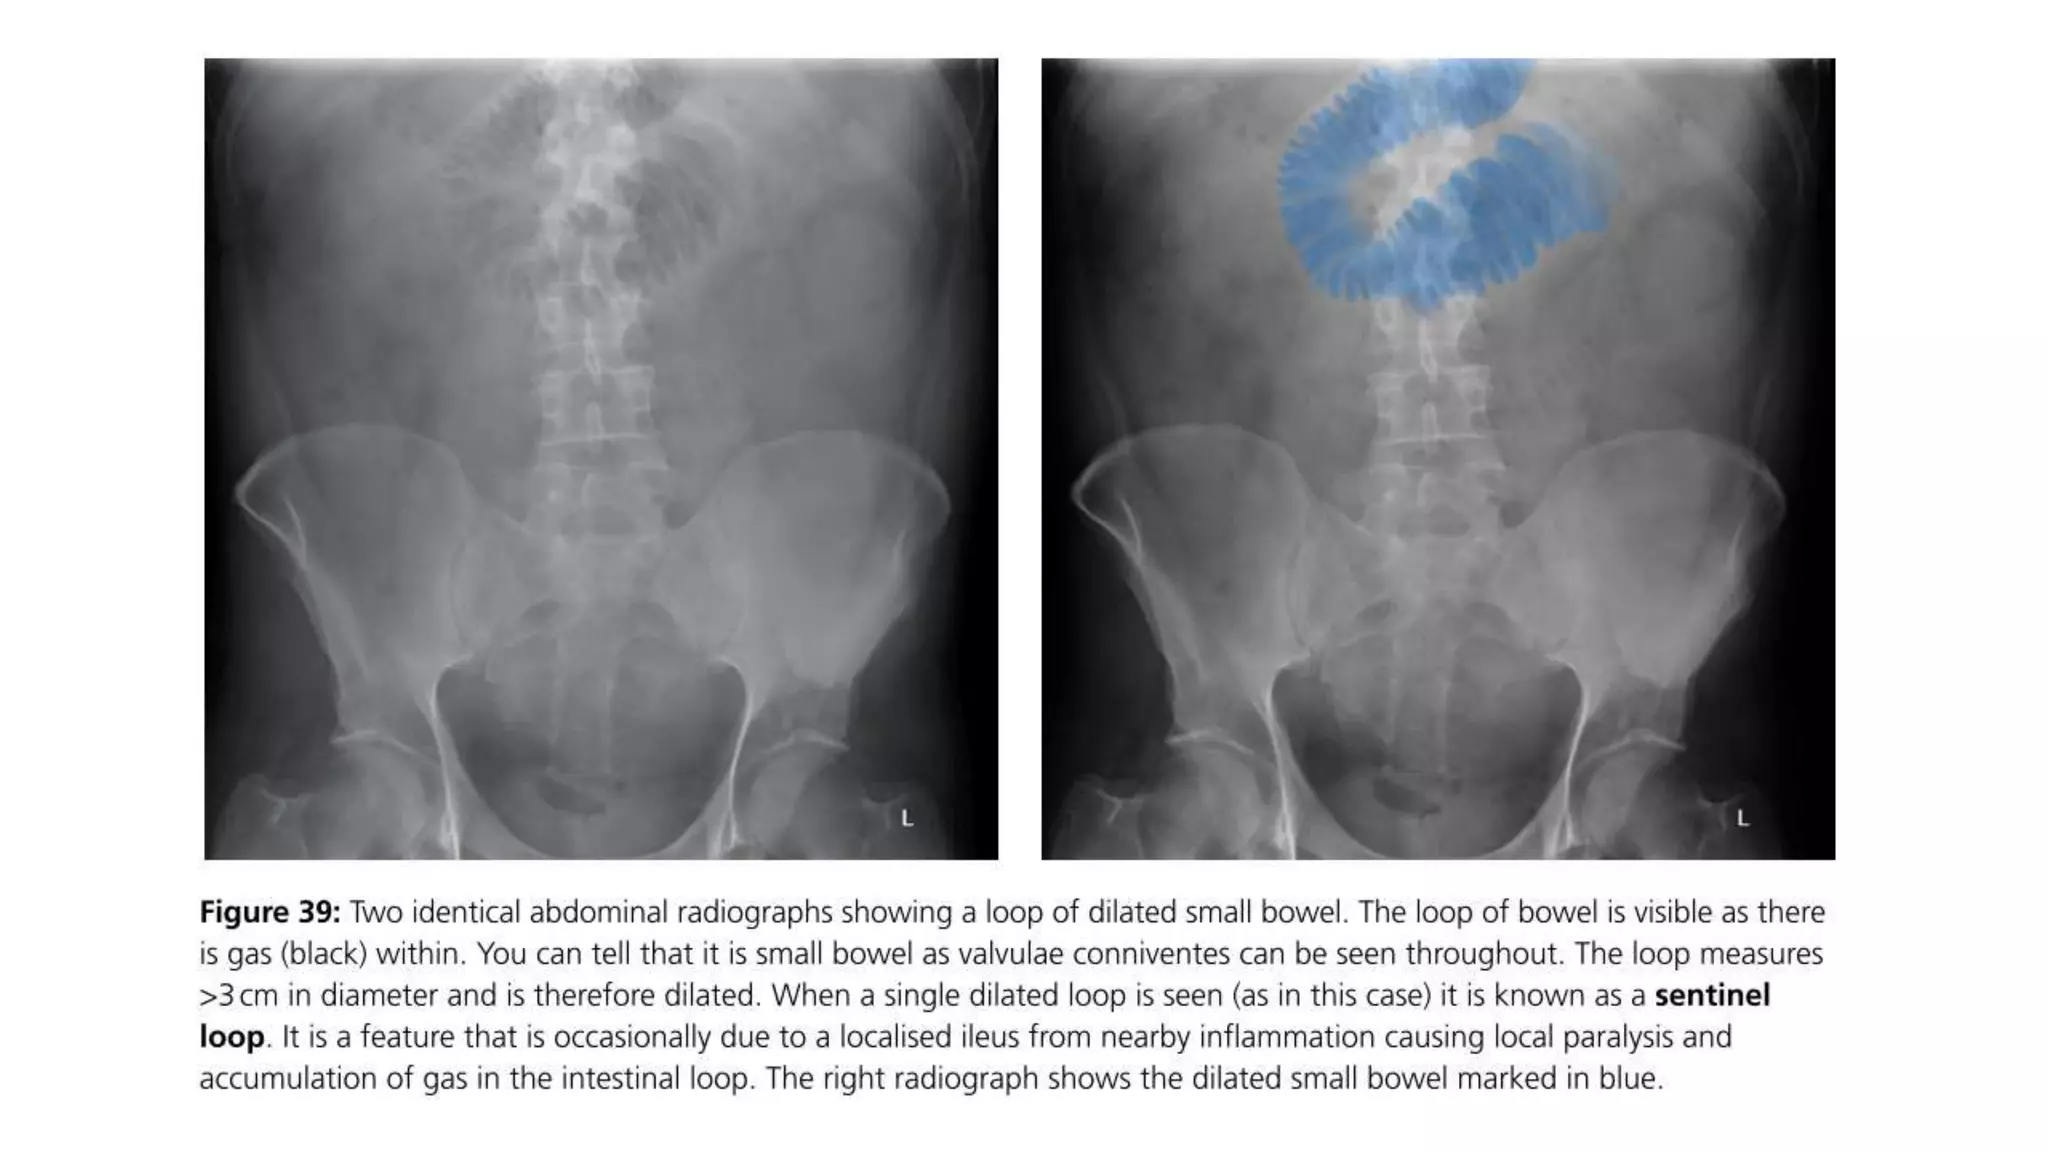

Radiological signs to look for:

• Dilation >3 cm: The small bowel is dilated if it measures over 3 cm in

diameter.

• Central location: The dilated loops are more likely to be centrally

located on the abdominal radiograph.

• Valvulae conniventes: These are the mucosal folds of the small

intestine. They are thin, closely spaced and classically seen as a

continuous thin line across the entire width of the bowel.

• Air fluid level in upright position